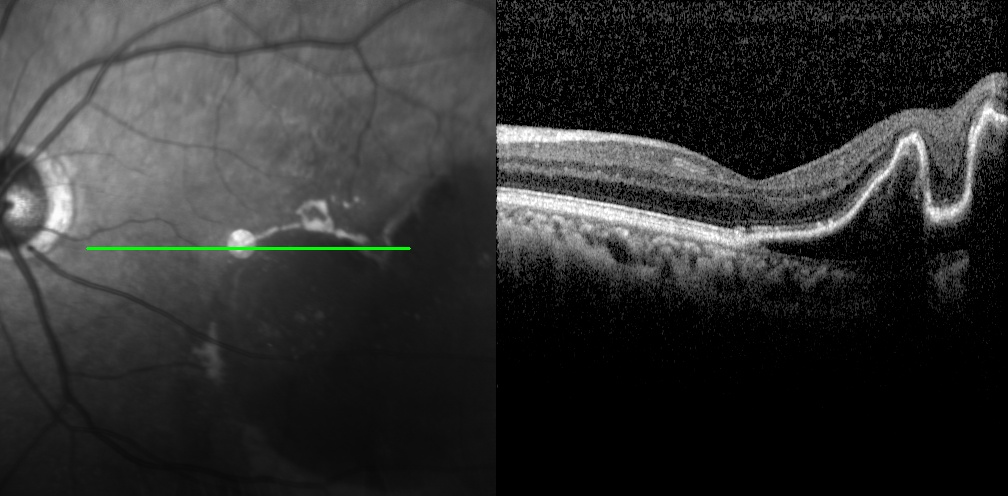

老王左眼檢查圖片

左眼調整用藥半個月后檢查圖片